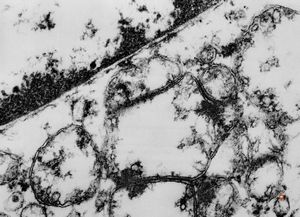

M,26y. | ribosome-lamella bodies in adenocarcinoma

M,41y. | ribosome-lamella complex in tricholeukocyte -hairy cell leukemia, spleen

M,41y. | ribosome-lamella complex in tricholeukocyte -hairy cell leukemia, spleen

M,41y. | ribosome-lamella complex in tricholeukocyte -hairy cell leukemia, spleen